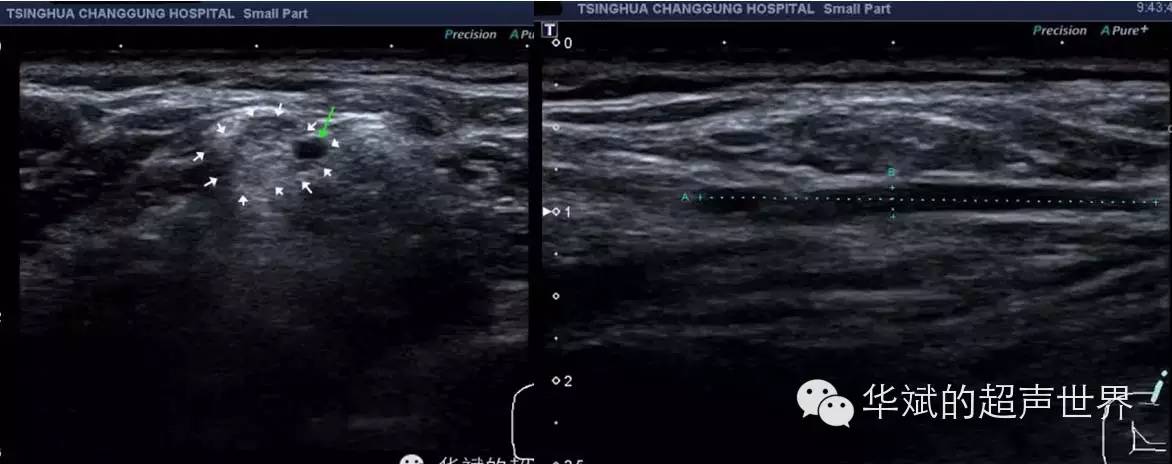

76岁女性,臂丛神经内的腱鞘囊肿.